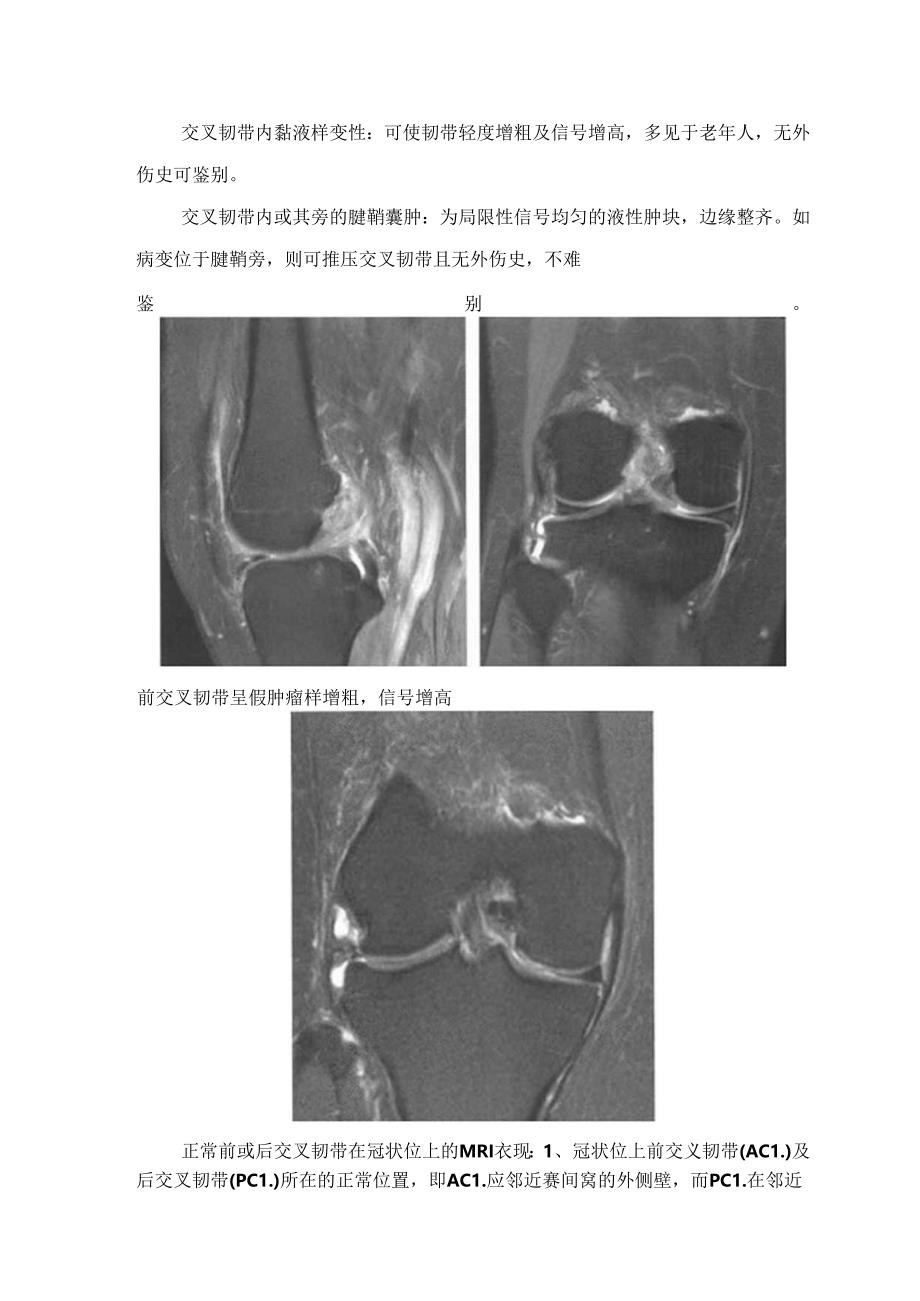

3、样变性:可使韧带轻度增粗及信号增高,多见于老年人,无外伤史可鉴别。交叉韧带内或其旁的腱鞘囊肿:为局限性信号均匀的液性肿块,边缘整齐。如病变位于腱鞘旁,则可推压交叉韧带且无外伤史,不难鉴别。前交叉韧带呈假肿瘤样增粗,信号增高正常前或后交叉韧带在冠状位上的MRI衣现:1、冠状位上前交义韧带(AC1.)及后交叉韧带(PC1.)所在的正常位置,即AC1.应邻近赛间窝的外侧壁,而PC1.在邻近微间窝的内侧壁处。2、正常时AC1.和PC1.边缘规整,呈低信号,在AC1.的低信号基础上,其内常见细小、规则脂肪间隔,此乃肌肉纤维间隔中含有薄层脂肪造成。3、AC1.和PC1.受到损伤(撕裂)时,韧带呈边缘不规则

4、、增粗或断裂,并失去正常低信号代之以病理性高信号征象。膝关节内侧或外侧副韧带撕裂膝关节内侧副韧带撕裂比外侧多见,正常侧副韧带在MRI上呈连续的条带状低信号影。其病因、MR1.征象等如下方表、图所示。内侧副韧带椭裂病因膝关节过度外翻MR1.征象例带连续性部分或全部中断.闪出MI水肿而增小.小度者可弯曲或呈波浪状.戊存的信号韧带内及其周困在TN1.及TjV1.上均出现高仔号伴随征象内恻半月板及周边大节囊附心部断裂或半小板及附后交外侧副韧带撕裂膝关节过度内翻韧带连续性部分或全部中断,因出血水肿而增粗,币:度者可弯曲或呈波浪状,残存的信号韧带内及其周围在TIw1.及T2WI上均出现高信号可伴交叉切带撕裂,胫骨外侧撕脱骨折(Scgond竹折).腓骨小头或邻近股骨骨折内、外侧副韧带撕裂MR1.表现:A、内侧副韧带撕裂:MR1.抑脂序列冠状位可见内侧副韧带中上部信号增高,局部信号欠连续,周困可见片状长T,长T,信号影。B、外侧副韧带撕裂:MR1.抑脂序列冠状位可见外侧副韧带迂曲、短缩,腓骨附着端信号增高,走行欠连续。